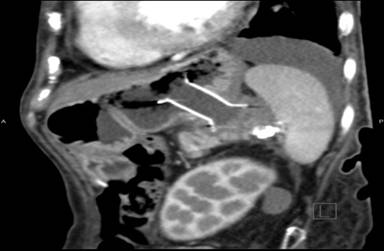

Three weeks later, she presented again with vomiting. EGD revealed that the stent had migrated into the stomach. This was subsequently removed and a larger diameter stent was inserted into the original tract, a Niti-STM Biliary Stent (NAGITM) (Taewoong-Medical Co, Seoul, South Korea), 16 mm in diameter x 30 mm in length. She was carefully followed up and nine months post procedure remained well. Her appetite was good and her abdominal discomfort had resolved. A recent repeat CT scan (Figure 6) showed that the stent was still in situ and the cyst had completely collapsed.

Figure 6. CT abdomen after 6 months of stent insertion showing stent in-situ and resolution of lesion. |